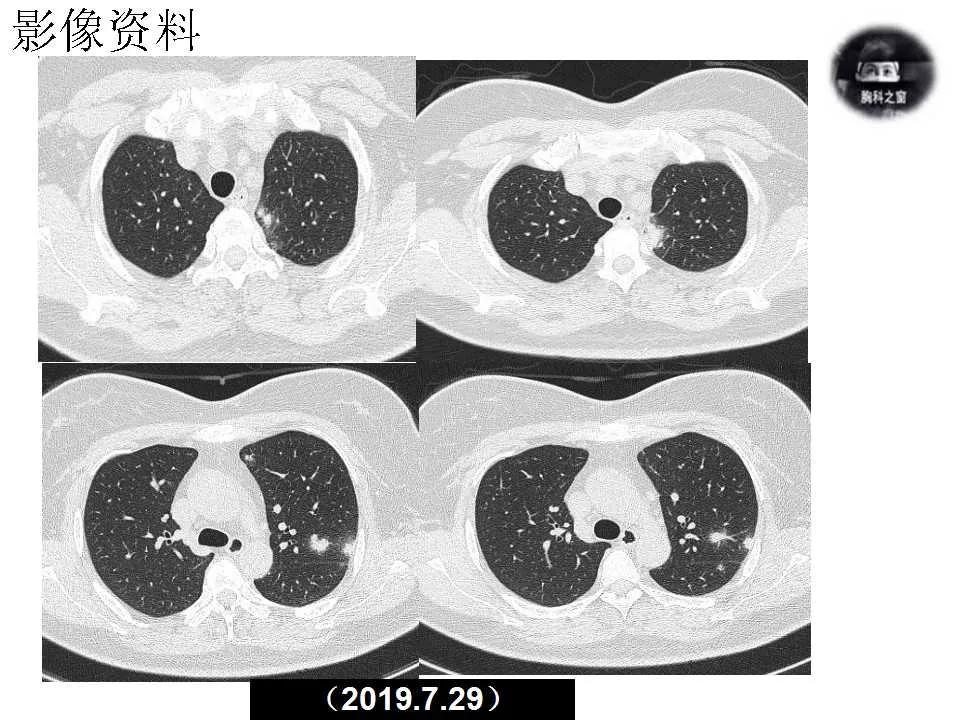

主诉:发现左肺病变1天

现病史:患者1天前体检胸部CT提示左肺病变,之前一段时间进食较少,七月初、七月中旬出现咳嗽、胸痛、无法深呼吸,无咯血,无乏力、盗汗,无明显体重减轻,为接受进一步诊治收入院。(2019.7.30)

影像诊断:真菌性肺炎,隐球菌可能性大。

追问病史,有近距离接触鸽子史。隐球菌抗原(+)。

肺隐球菌病